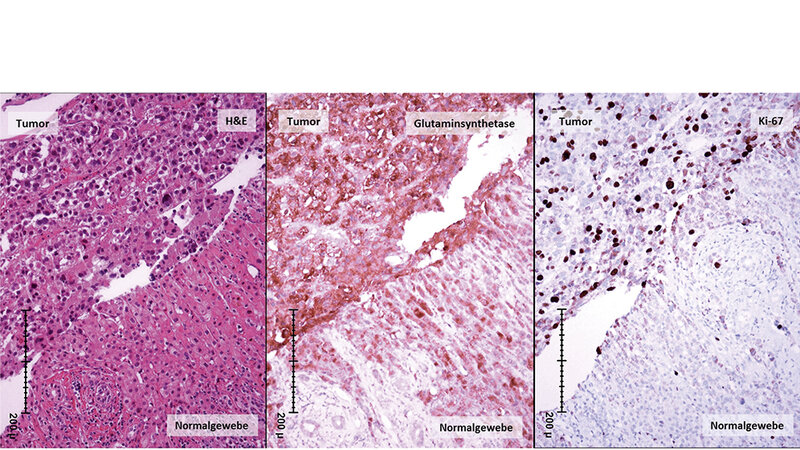

Die Leber ist die größte Drüse des Körpers, ist an einer Vielzahl von Stoffwechselprozessen beteiligt und produziert wichtige Enzyme und Eiweiße.

Sie ist ein Entgiftungsorgan, bildet Gallenflüssigkeit, verarbeitet Bilirubin als Abbauprodukt der roten Blutkörperchen et cetera. Sie erfüllt sehr viele Aufgaben im Körper und speichert unter anderem das Glykogen und Vitamine, die über die Pfortader aus dem Darm herantransportiert werden.